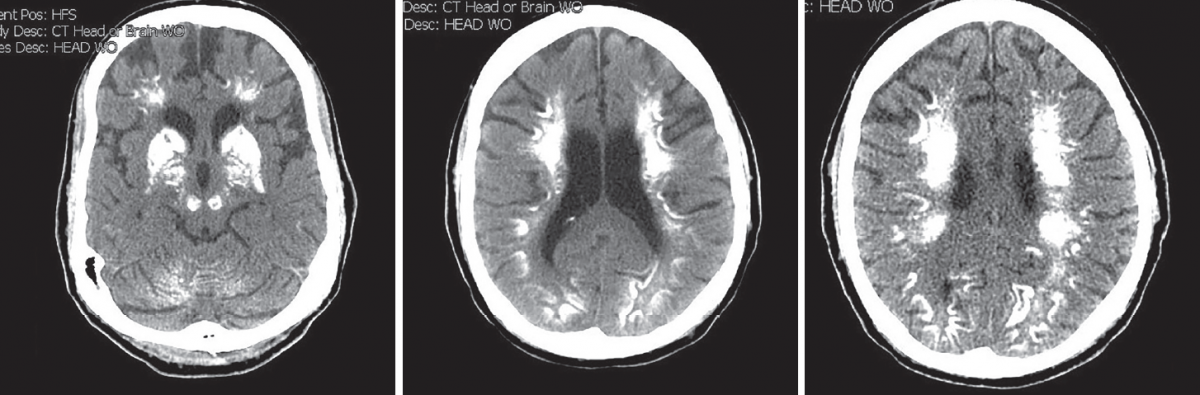

Michael Lienhard, MS-IV; Zhigang Yuan, MD; Spencer Knox, MD; Jorge C. Parellada, MD

A 44-year-old woman presented to the emergency department with a 1-day history of acute mental status changes, headache, neck pain, and fever.